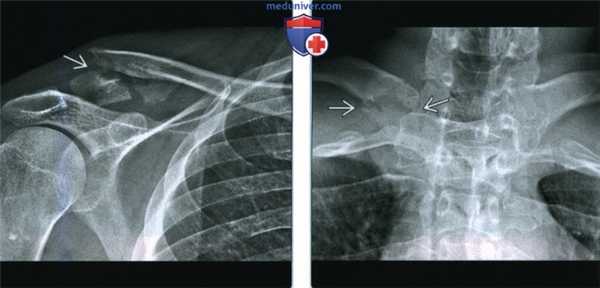

(Слева) На передне-задней рентгенограмме определяется промежуток между правой ключицей и грудино-ключичной суставной поверхностью. Левый грудино-ключичный сустав между ключицей и грудиной нормальный. Это вывих III степени с разрывом грудино-ключичных связок, суставной капсулы и разрывом реберно-ключичных связок.

(Справа) На осевой КТ у этого же пациента визуализируется медиальный конец правой ключицы, вывихнутый латерально и несколько кпереди. Большинство грудино-ключичных вывихов являются передними. Обратите внимание на нормальный левый грудино-ключичный сустав. (Слева) На фронтальной КТ с реформатированием у этого же пациента определяется расширение правого грудино-ключичного сустава.

(Справа) На передне-задней рентгенограмме у другого пациента определяется промежуток между левой ключицей и суставной поверхностью грудино-ключичного сустава. Правый грудино-ключичный сустав между ключицей и грудиной нормальный. Это тоже вывих III степени с полным разрывом грудино-ключичных связок. Важно оценить грудино-ключичный сустав на рентгенограммах при травме грудной клетки, учитывая риск травмы сосудов. (Слева) На фронтальной КТ с реформатированием у этого же пациента определяется неправильное положение левой ключицы относительно суставной поверхности грудины. Обратите внимание на нормальный правый грудино-ключичный сустав.

(Справа) На осевой КТ ангиограмме у этого же пациента определяется заднее положение ключицы относительно грудино-ключичного сустава. Медиальный конец ключицы лежит рядом с плечеголовной веной, но повреждения сосудов не отмечено. Задние вывихи более тяжелые, поскольку они могут вызвать жизнеугрожающее повреждение сосудов средостения.

3. КТ при травме грудино-ключичного сустава:

• Компьютерная томография с контрастированием:

о Можно выявить травму сосудов и мягких тканей

о Легко определяется направление вывиха:

- Сравнивают с противоположной нормальной стороной

о Полезна при планировании операции

о Можно быстро получить данные в условиях травмы